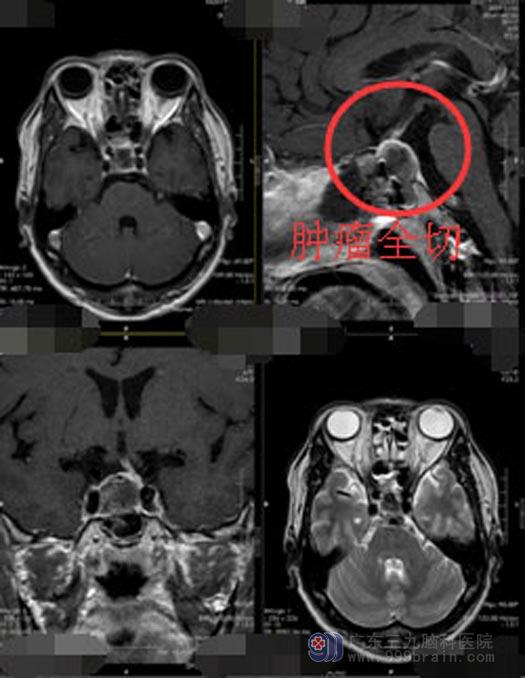

脑垂体瘤的治疗刻不容缓,经鼻蝶手术是最佳的治疗方案,该手术具有创伤小,并发症少,恢复快等特点。得到潘大哥和家人的同意后,垂体瘤诊治中心的手术团队为他实施了“内镜经鼻蝶鞍区垂体腺瘤切除术”。手术过程很顺利,肿瘤被完整的切除。

术后的潘大哥恢复得很好,头痛头晕症状消失,也没有了烦渴、多饮、多尿。

▲手术后